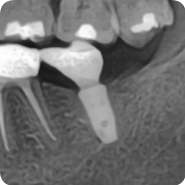

임플란트 커스커마이즈드 어버트먼트 (customized abutment)를 이용한 임플란트 크라운 보철

하악 좌측 제2대구치의 임플란트가 보철 크라운까지 모두 마무리된 모습입니다. 임플란트는 크게 3개의 파...